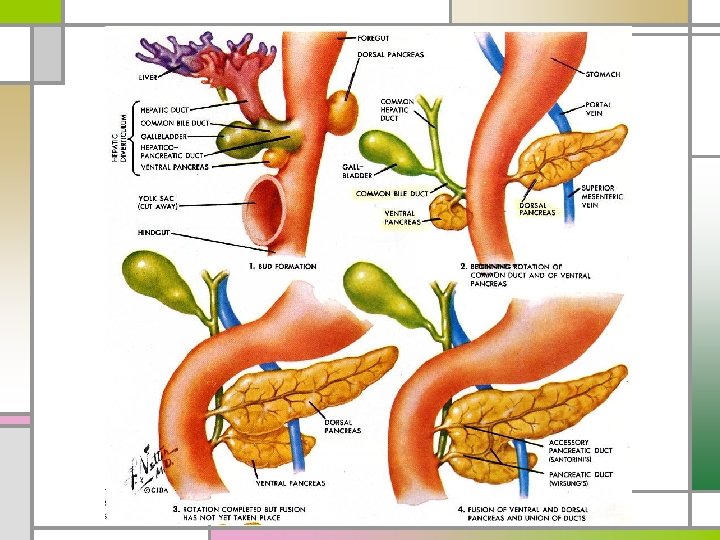

Pancreas Divisum n Embryologic ventral & dorsal pancreatic anlagen fail to fuse pancreatic drainage through the accessory papilla n M/C congenital anatomic variant of the human pancreas n Combination of pancreas divisum & small accessory orifice dorsal duct obstruction pancreatitis